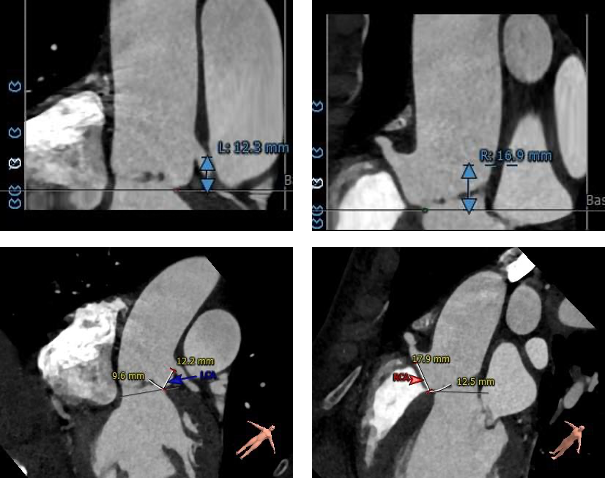

对于单纯返流患者来说,术前也分析了瓣膜移位的风险比较高。结合术前的分析与术中的情况,为保证患者的治疗效果,术中进行了“瓣中瓣”的策略,即第一个瓣膜在非稳定状态下作为锚定骨架,便于第二个瓣膜顺利植入并重建血流动力学。

球囊后扩后,瓣膜与周围组织贴合的更好。术后即刻造影结果显示无瓣周漏,工作瓣膜形态优异。术中测量结果显示即刻跨瓣压差降至10mmHg,舒张压从术前35mmHg左右上升到60mmHg以上,术后患者症状明显改善。